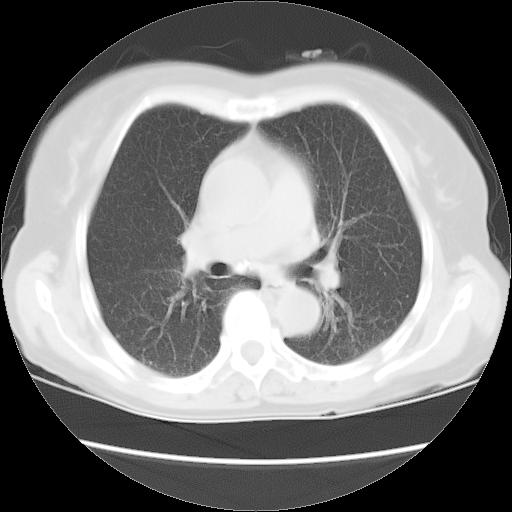

以下是引用夏季在2007-9-18 11:00:00的发言:[br]1。右肺肿块,周围有短毛刺,肺门侧有血管与其相连,胸壁侧有胸膜凹陷征,考虑周围性肺癌 2。左侧甲状腺软组织肿块,内有高密度钙化灶,考虑左侧甲状腺腺瘤。

以下是引用卜一在2007-9-18 14:41:00的发言:[br]右肺肿块:毛刺+胸膜凹陷征+供血血管+浅分叶+强化。支持:周围性肺癌 !另:左侧甲状腺腺瘤!